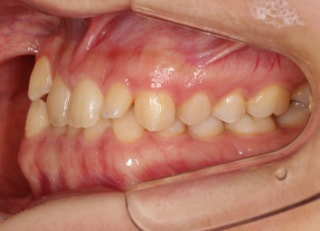

治療前

治療後(2年11ヶ月後)